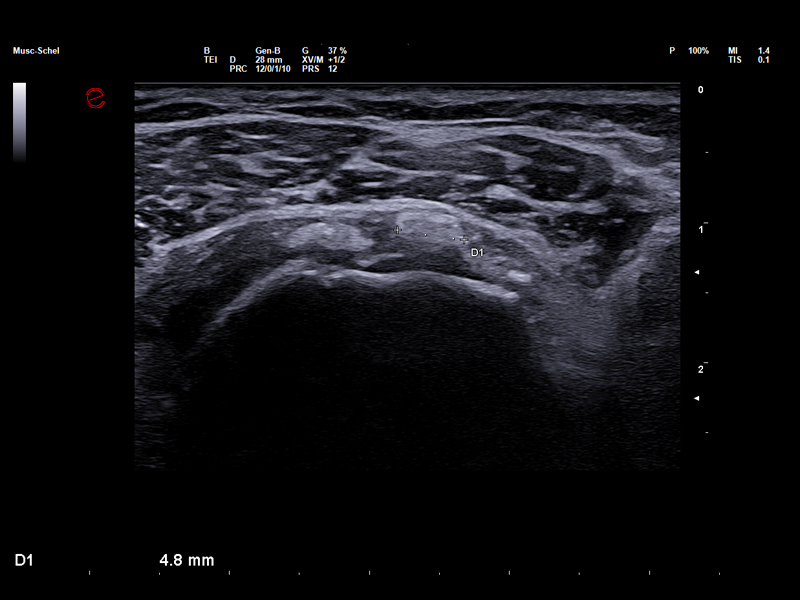

High-Frequency imaging for sport injury detection

Thanks to the advanced image quality of Esaote’s high-frequency probes, which operate at frequencies of up to 25 MHz, even micro-lesions can be clearly and precisely identified before they evolve into more serious injuries, thus empowering clinicians to stay one step ahead in injury prevention and management. The Very-High Frequency hockey stick probe, IHX 6-25, combines outstanding spatial resolution with advanced ergonomic design to facilitate needle access and perform accurate interventional gestures with millimetric precision.